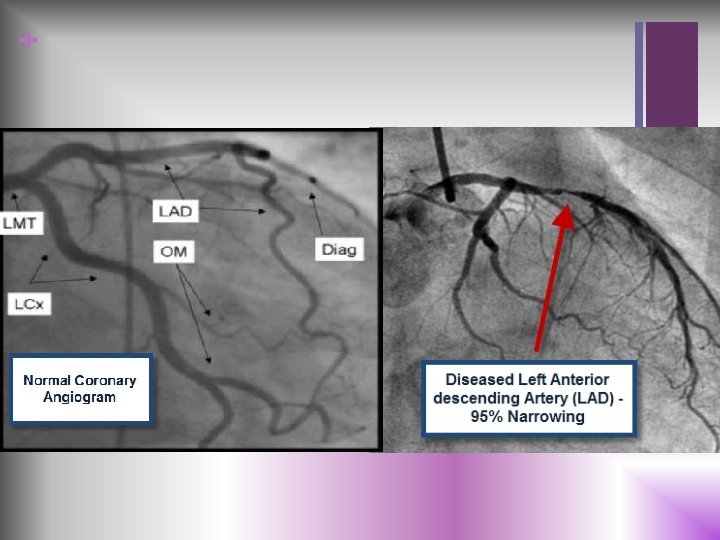

+ n ECD Important Tests or EKG (electrocardiogram) n Echocardiogram n Exercise n Chest stress test X-ray n Cardiac catheterization n Coronary angiogram